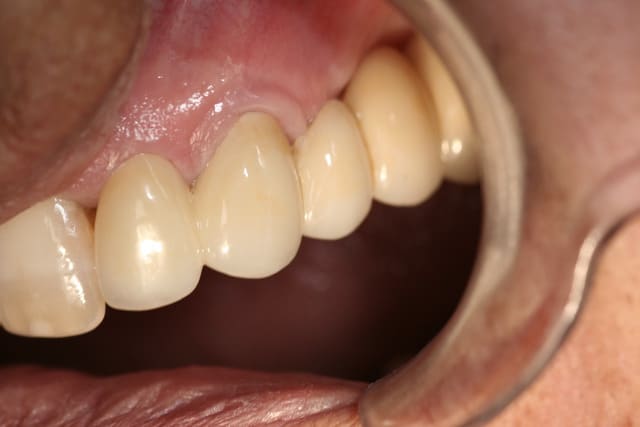

J'ai le plaisir de vous présenter un cas clinique de couronne E-Max sur 22 réalisé à partir de l'empreinte optique intra-buccale.

sur la photo "maquillage" on voit que le bord du provisoire a été un peu envahissant sur la canine, avec le bridge définitif la gencive est revenu a sa place, avec des bords foireux la gencive ne revient pas

Joli bridge.